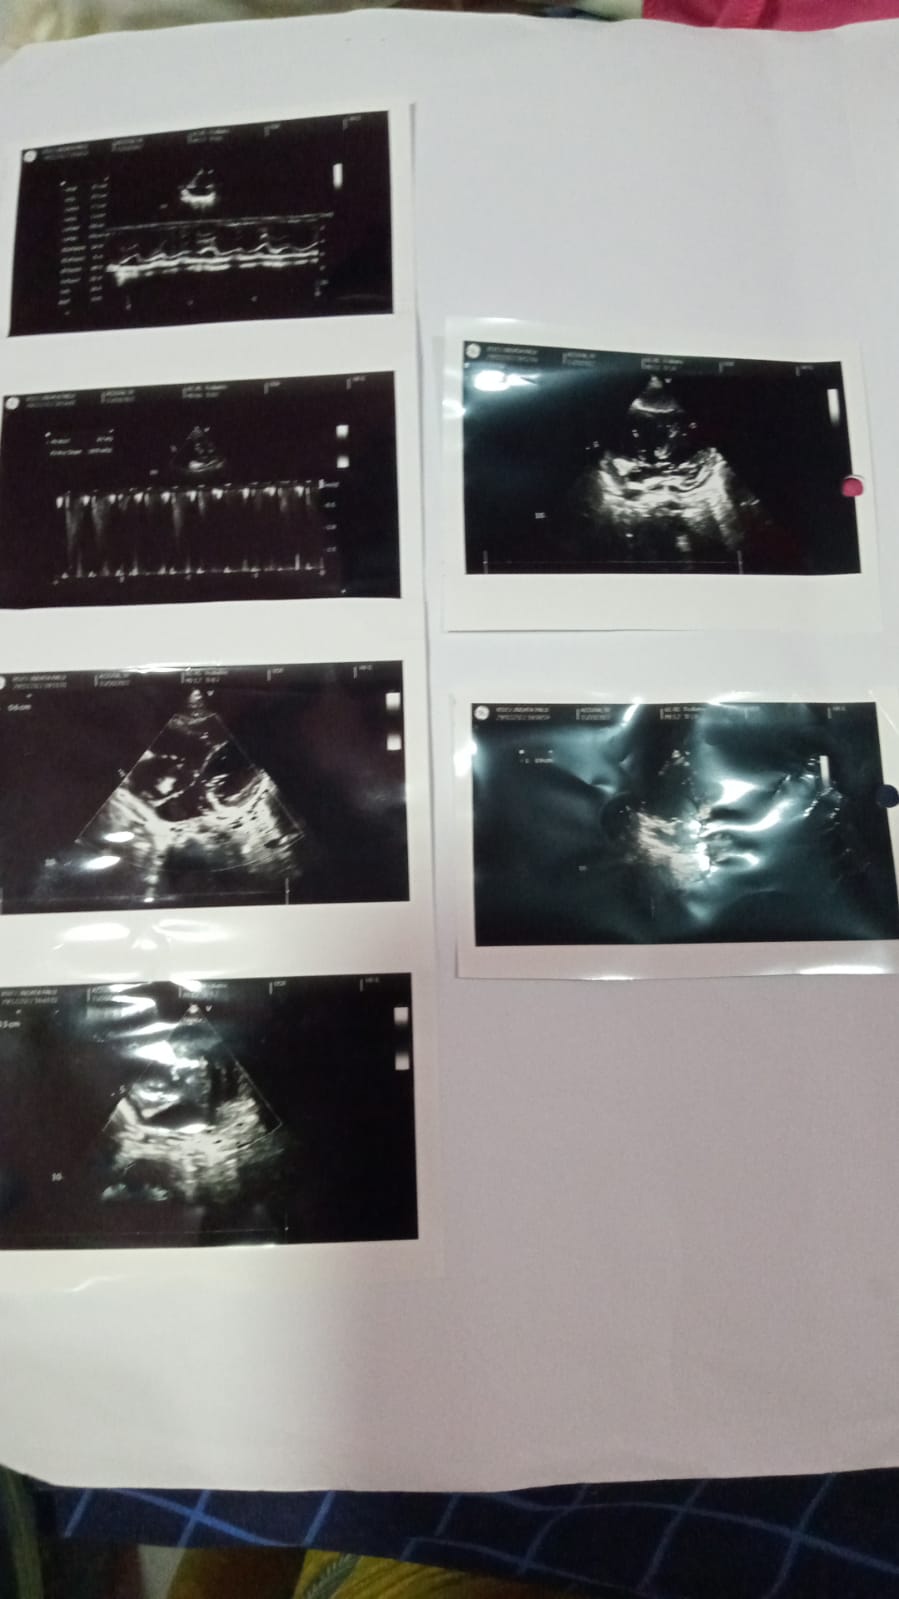

Kami orang tua merasa aneh ketika Azzura sulit sekali minum asi dan mengalami BAB yang tidak wajar sampai menghabiskan 10 diapers. Kami membawanya ke IGD RS Anutapura dan langsung dilakukan X-Ray, hasilnya anak kami mengalami infeksi paru-paru efek pneumonia. Dokter meminta agar di-echo juga, benar saja ketahuan kalau Azzura mengidap kebocoran jantung VSD dan ASD.

Kondisinya baik setelah operasi selama 2 jam dan masuk ICU selama 15 hari. Setelah itu kami dijadwalkan lagi untuk kontrol ke poli bedah dengan tujuan pencabutan benang operasi dan ke dokter jantung untuk di-echo kembali, memastikan kondisi pasien pasca operasi.

Senin, 25 Agustus 2025 kemarin, ananda Azzura menjalani kontrol ke Poli Jantung di RSU Palu. Alhamdulillah, kondisi Azzura menunjukkan perkembangan yang baik. Namun, berdasarkan hasil echo, katup jantung Azzura belum pulih sepenuhnya karena masih terdapat tarikan benang bekas jahitan yang saling menarik. Oleh karena itu, dokter jantung tetap menyarankan agar Azzura melanjutkan terapi obat jantung seperti sebelumnya.

Alhamdulillah, pada tanggal 6 Maret 2024, Azzura sudah operasi jantung VSD Repair di RS Jantung Harapan Kita. Proses pemulihannya pun berjalan lancar, dan kami sangat bersyukur atas kemajuan ini.

Aku selaku orang tua Azzura ingin mengabarkan keadaan anakku ya. Alhamdulillah puji syukur anakku Azzura sudah semakin membaik kondisinya pasca operasi untuk yang ke 2 kalinya yaitu operasi vsd repair. Saturasi Azzura alhamdulillah juga melebihi target yang ditetapkan oleh dokter yaitu dari 75% menjadi 97% setelah menjalani operasi.